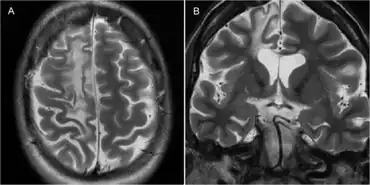

Rasmussen encephalitis resulting in atrophy of the right frontal lobe as seen on MRI.[1]

The diagnosis may be made based on the symptoms alone, after ruling out other possible causes. An EEG will usually show the electrical features of epilepsy and slowing of brain activity in the affected hemisphere, and MRI brain scans will show gradual shrinkage of the affected hemisphere with signs of inflammation or scarring.[14]